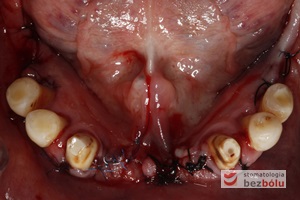

Żuchwa - widok powierzchni okluzyjnej - symetryczne braki zębowe w zakresie 4 siekaczy i trzonowców

Żuchwa – widok powierzchni okluzyjnej – symetryczne braki zębowe w zakresie 4 siekaczy i trzonowców

Braki zębowe w strefach bocznych szczęki i żuchwy - widoczne starcie patologiczne na skutek przeciążeń okluzyjnych w odcinku przednim

Braki zębowe w strefach bocznych szczęki i żuchwy – widoczne starcie patologiczne na skutek przeciążeń okluzyjnych w odcinku przednim